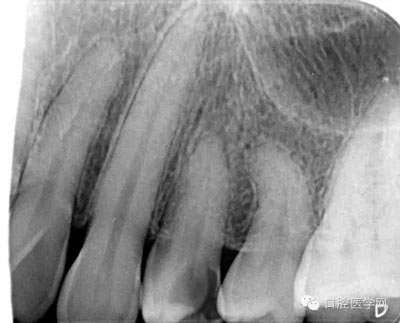

第一步:拍攝X線片,觀察髓腔形態(tài)以及根管走向,疑似根管長度較短且彎曲。

檢查:24遠中鄰合面見一黃豆大小齲洞,探及穿髓孔,叩(-),松動(-),冷熱診劇烈疼痛,牙齦正常。